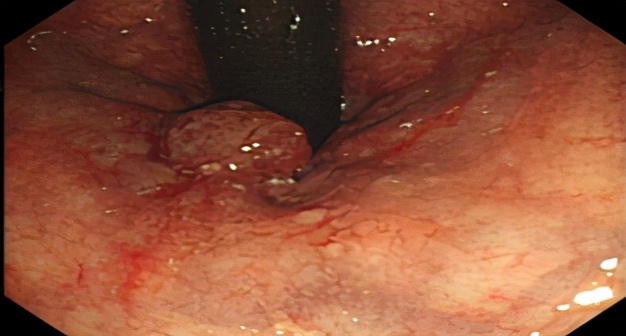

图2. 治疗后4年余肠镜未见复发征象(2020.11)